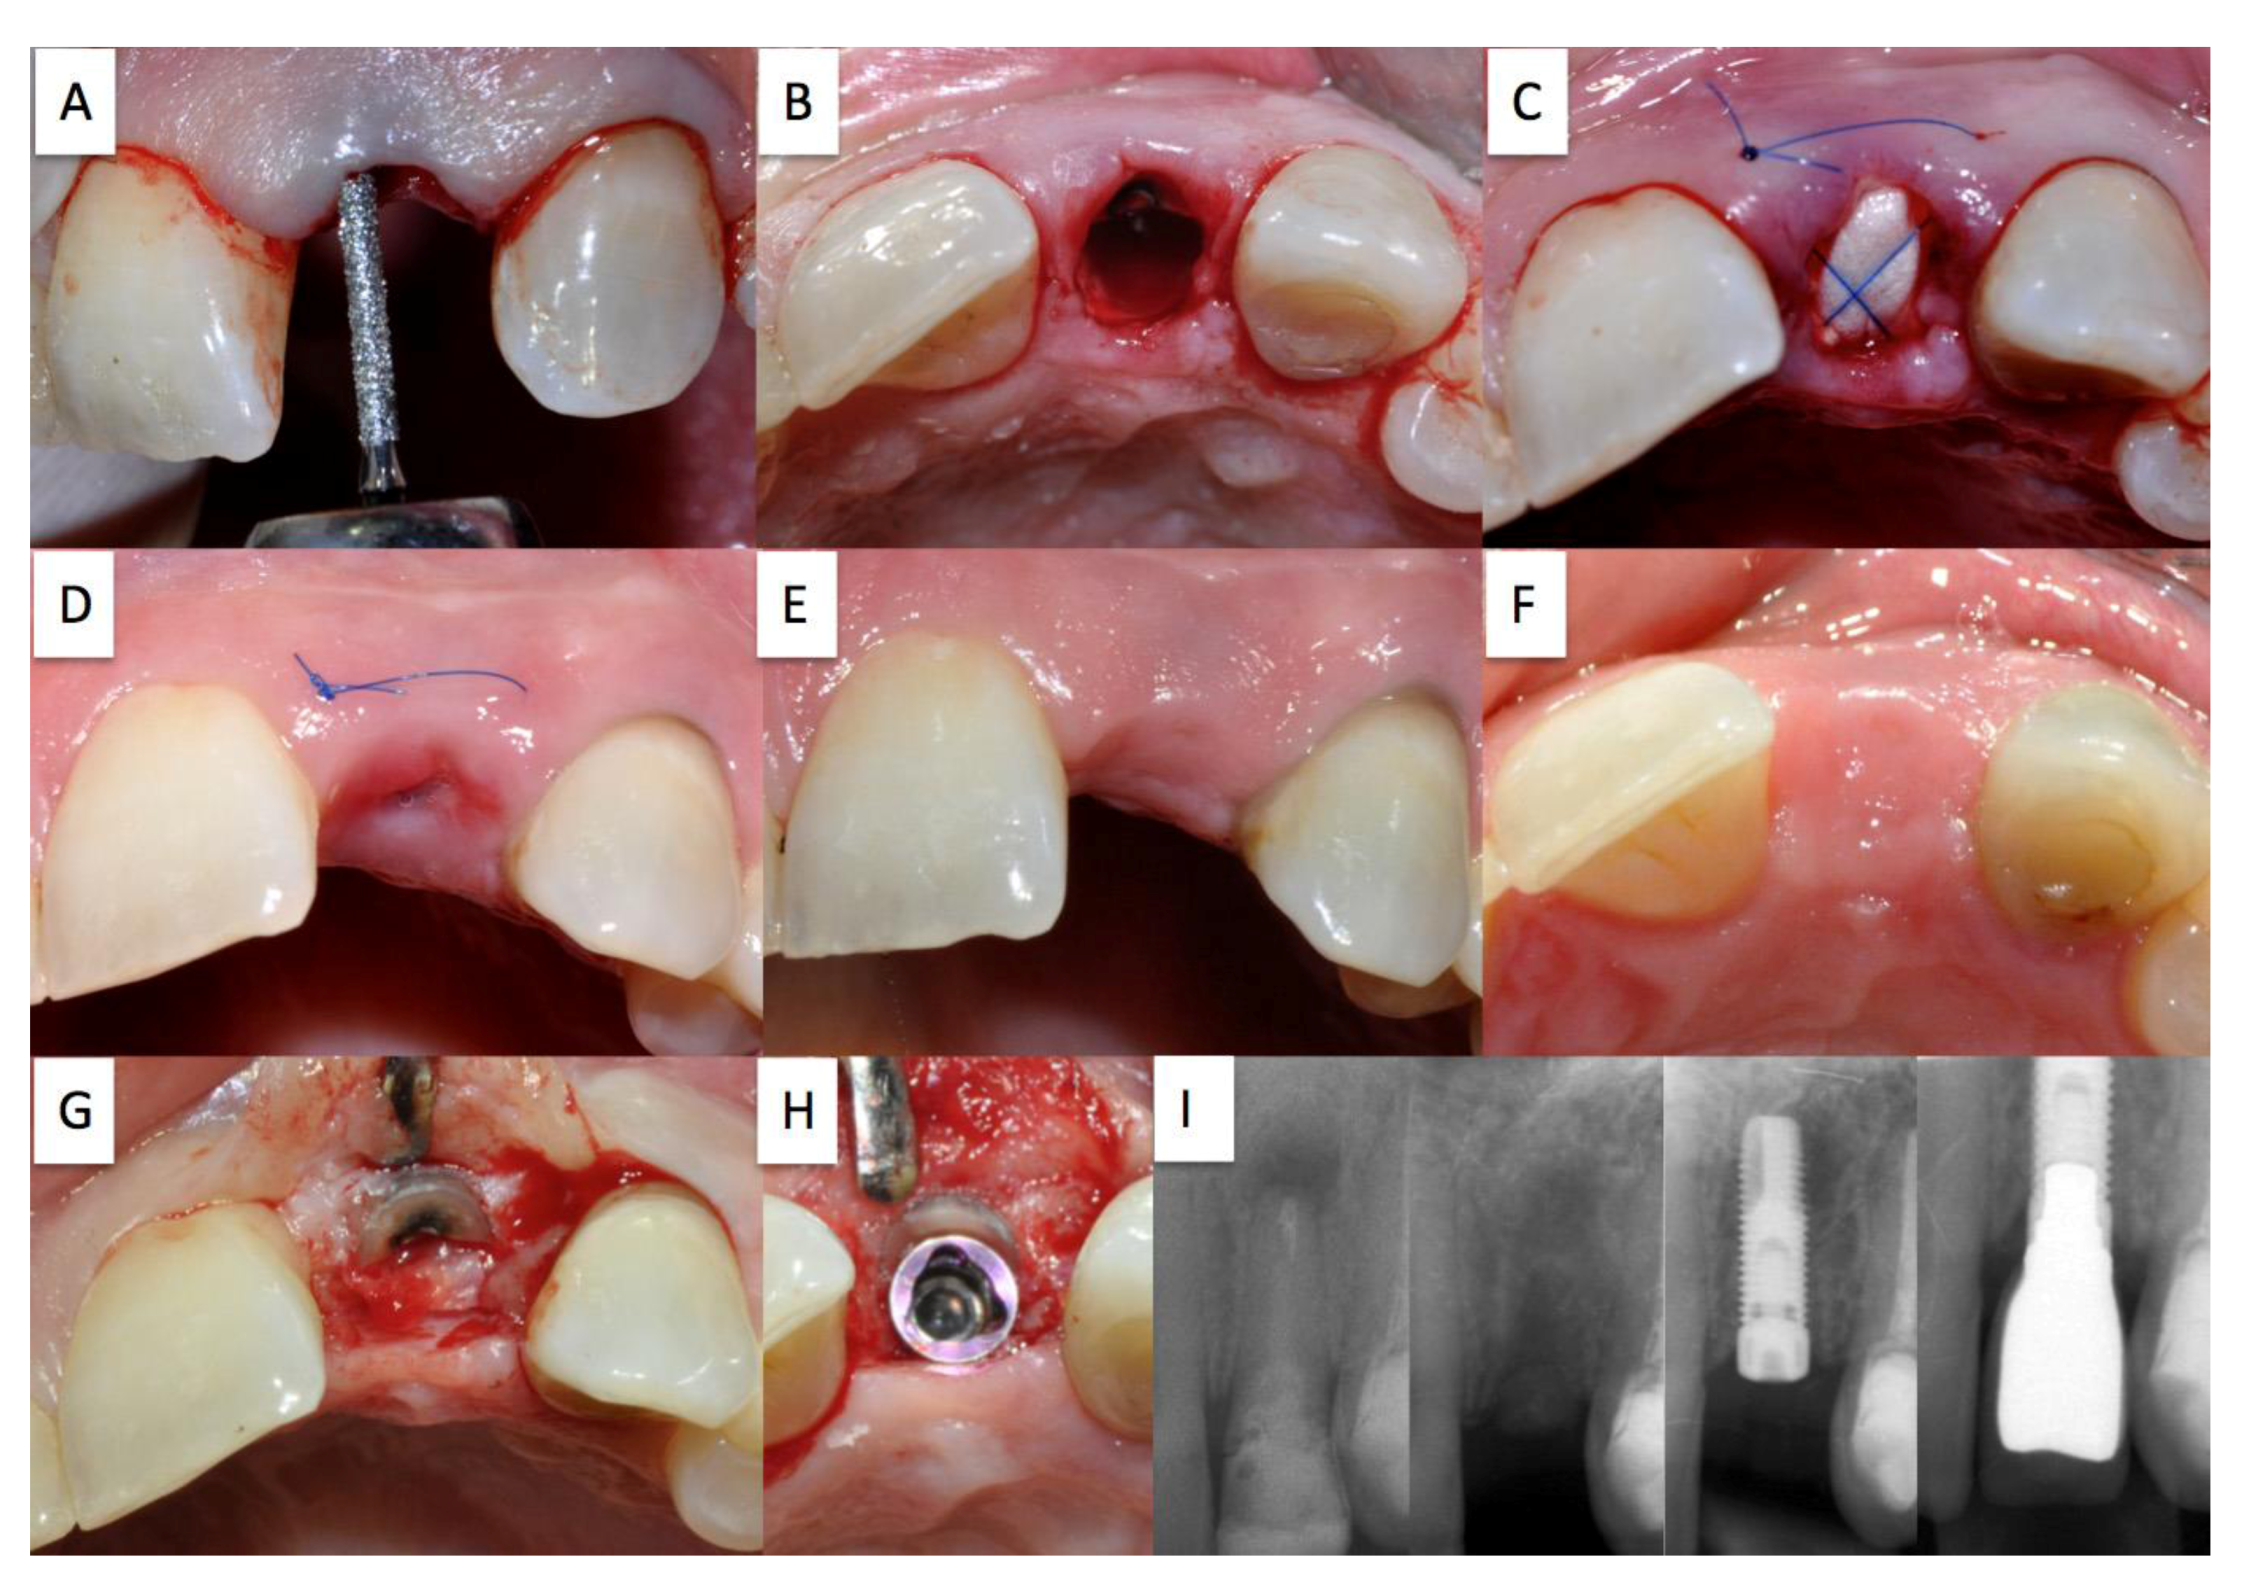

Treatment plan: Cutting of the bridge distal of abutment 12 and partial root extraction of tooth 13, prevention of alveolar ridge resorption using the socket shield technique, late implantation at region 13 (Nobel Biocare Replace®). The treatment is depicted in Figure 2.

Figure 2. Case 1.

Dentistry 02 00011 g002

Status post extraction with retention of the shortened and reduced root fragment (A); Absorbable cone inserted into the extraction socket secured with criss-cross suture (B); healing course following suture removal after 10 days (C); possible perforation of the buccal mucosa by the socket shield (D); completely preserved buccal bundle bone with re-entry (E); optimum, slightly palatial shift of the implant, jumping distance between implant and socket shield was filled with Bio-oss® (G); pre-operative X-ray control, with socket shield in the healing phase, with inserted implant, with screwed crown (H).